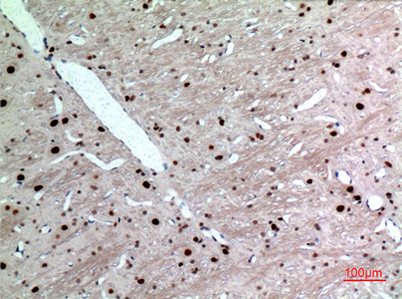

| Dilutions: | Western Blot: 1/500 - 1/2000. IHC-p: 1:100-300 ELISA: 1/20000. Not yet tested in other applications. |